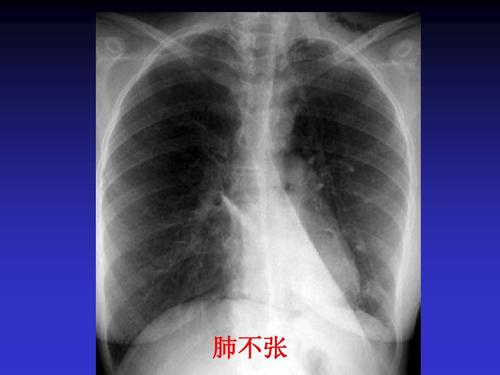

肺不张